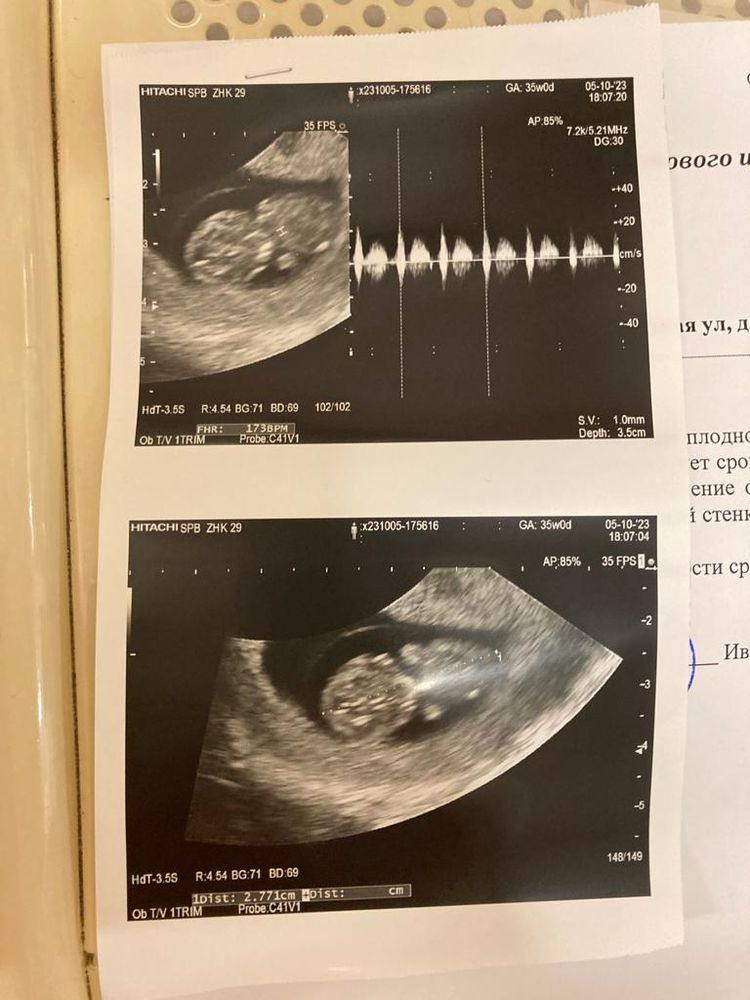

Узи на 9+5 неделе

Изображение

На 8 неделе узи: малыш на 7 +4 недель ктр 13,6 мм, на 9+5 неделе малыш на 9+4,ктр 27,7 мм сердцебиение 173 удара.